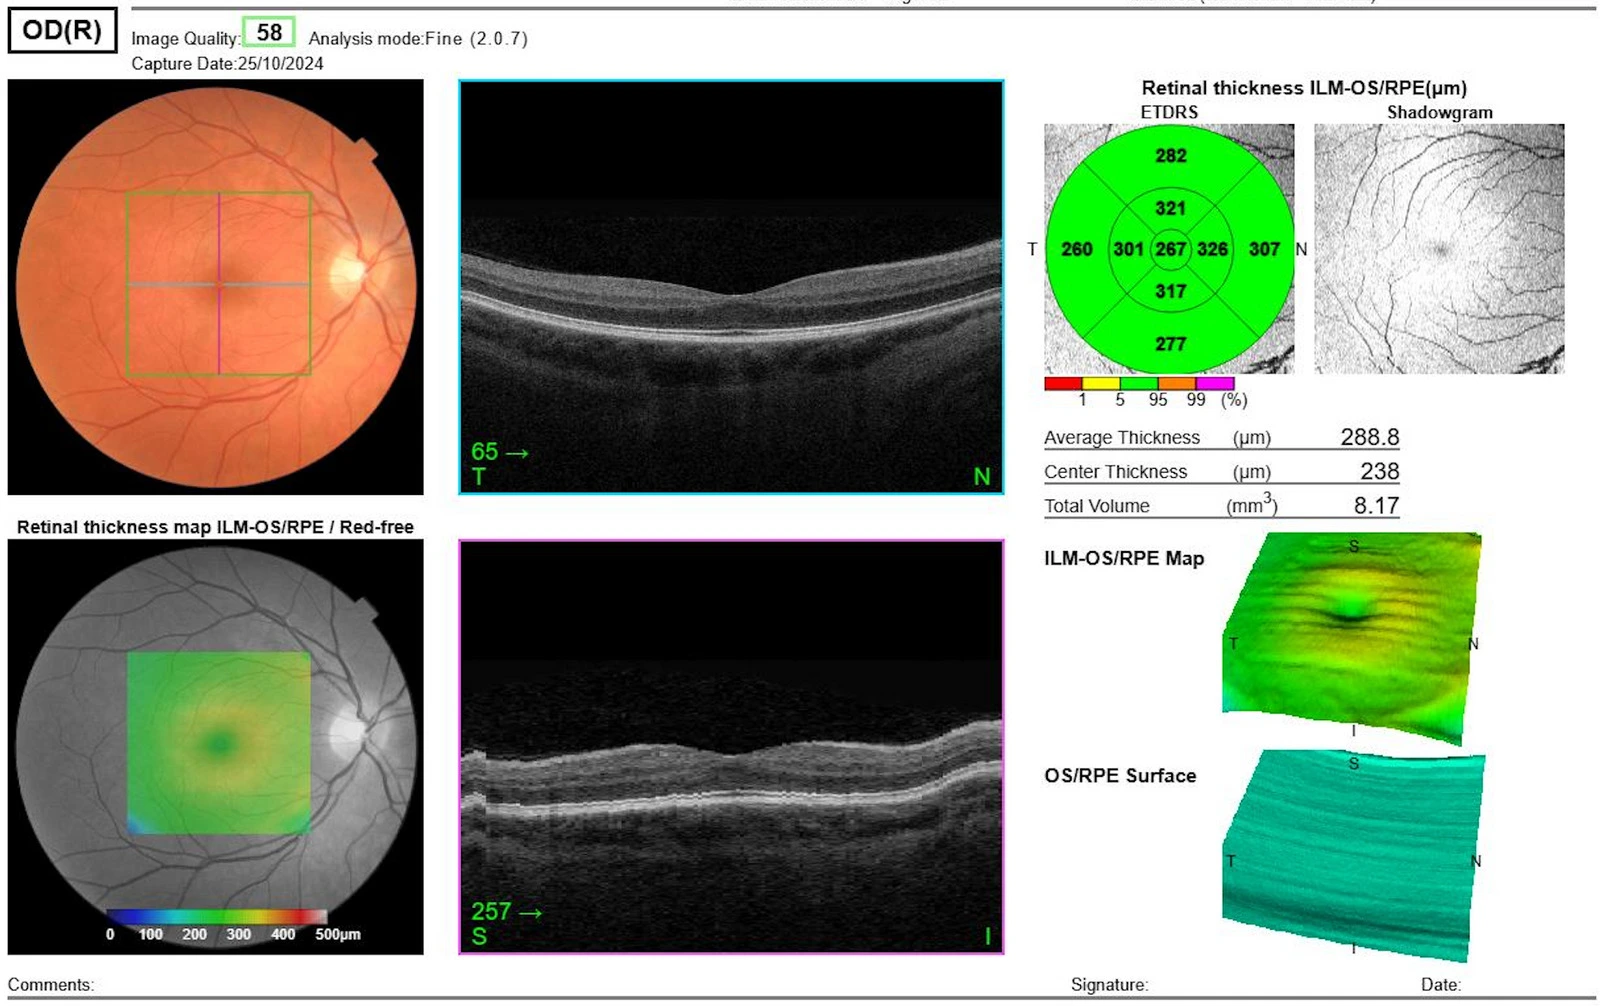

Wir schauen uns im Detail die einzelnen Zellschichten Ihrer Netzhaut an und entdecken dadurch kleinste Veränderungen häufig bevor Sie Symptome haben. Mit unseren modernen Ultrawide-Aufnahmen müssen Sie nicht mal mehr Pupillen erweiternde Tropfen bekommen – d. h. keine Ausfallzeiten für Sie und bequemes Anreisen mit dem Auto ist auch möglich.

In der Feinschicht Aufnahme (OCT)

werden

selbst kleinste

Veränderungen der Netzhaut sofort

sichtbar.